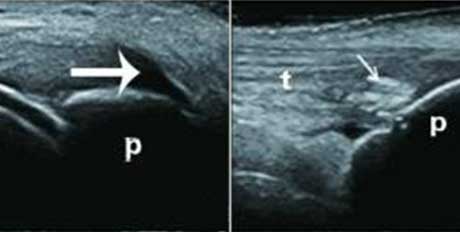

聚集体

髁软骨的双轨征状,显示髌腱内部的聚集体